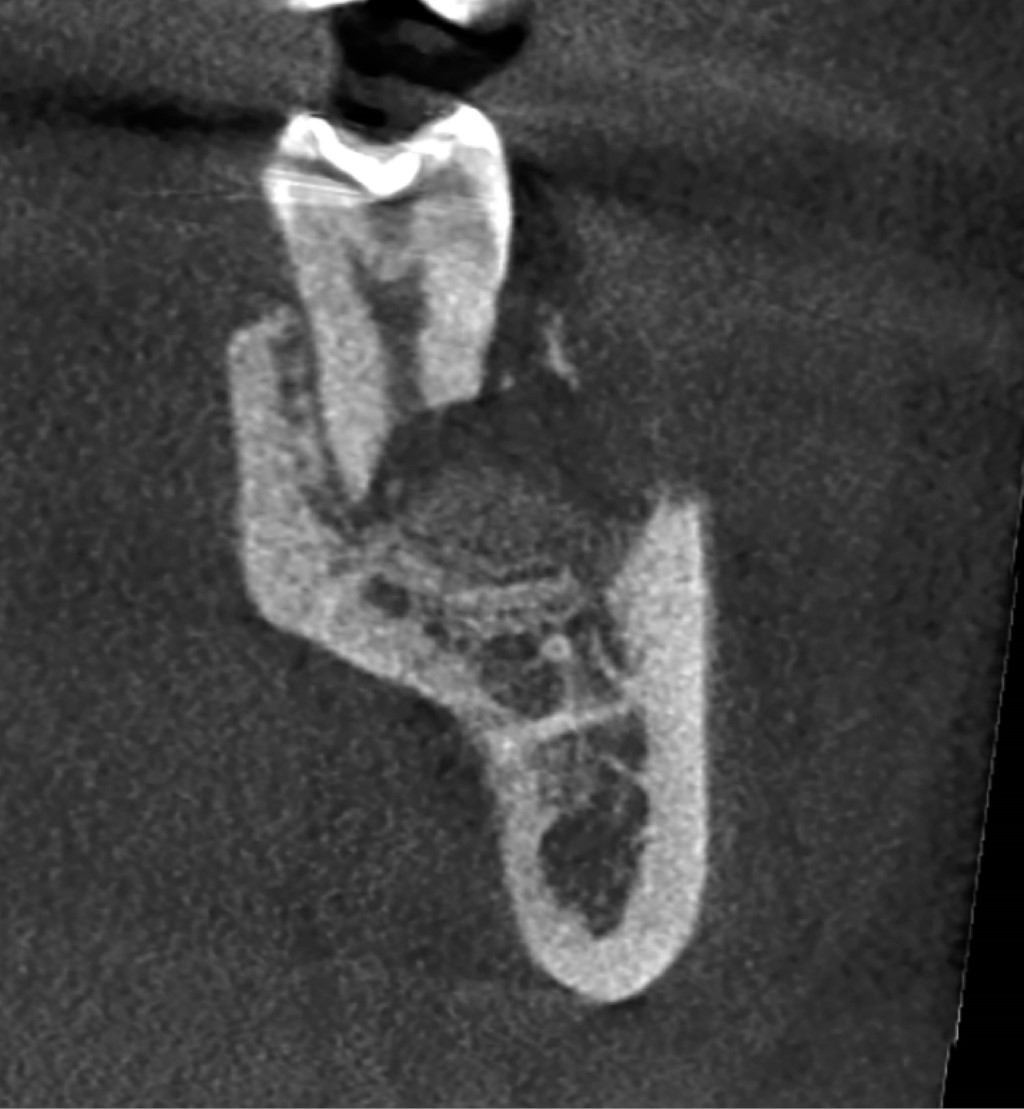

Las imágenes de reconstrucción 3D muestran pérdida de cortical vestibular en la zona del tercer molar, de forma redondeada, compatible con la forma de la corona del tercer molar extraído previamente, así como reabsorción de los tercios medio y apical de la raíz distal del segundo molar, observando que la reabsorción no se presenta de forma simétrica, la pared lingual de la raíz se extiende aproximadamente al tercio medio, no así la pared vestibular de la misma raíz que solamente está presente hasta el tercio coronal (Figuras 3 y 4).

La proyección coronal de la tomografía comprueba lo anterior, además muestra un conducto distal amplio que se extiende solamente hasta el tercio coronal radicular (Figura 5).

Por su parte, en la proyección sagital se observa que la pared mesial de la raíz distal termina aproximadamente en el tercio medio radicular y la pared distal tiene su nivel en el tercio coronal (Figura 6).

Figura 3

Figura 4

Figura 5

Figura 6